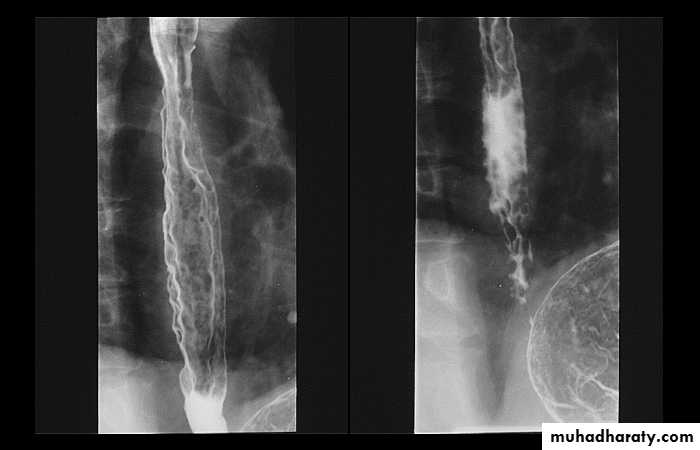

ESOPHAGEAL WEB

10% incidence at autopsy

Can be congenital or acquiredMost in hypopharynx and proximal esophagus

Majority protrude from anterior esophageal wall

Symptoms if lumen > 50% compromised

Sideropenic dysphagia (Plummer-Vinson syndrome)

Iron deficiency anemia

Esophageal web with dysphagia

Increased incidence of carcinoma

Validity of syndrome debatable